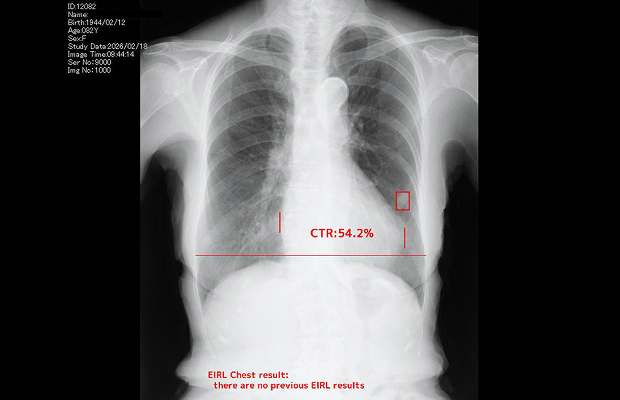

AIの眼が、肺がん検診の精度を 革新する。

「大切な健康を、より確かな精度で守りたい」ーその想いに応えるために。当院では、胸部X線検査において最新の「AIサポート型 肺がん診断」を導入しています。

日本人の死因第1位である肺がんは、進行とともに生存率が大きく低下するため、微細な肺結節を逃さない「早期発見」が何より重要です。

医師の確かな知見にAIの高度な解析力を掛け合わせることで、診断の精度を飛躍的に向上。私たちは最先端の技術を活用し、お一人おひとりの安心と、健やかな未来のために全力を尽くし、積極的にサポートいたします。